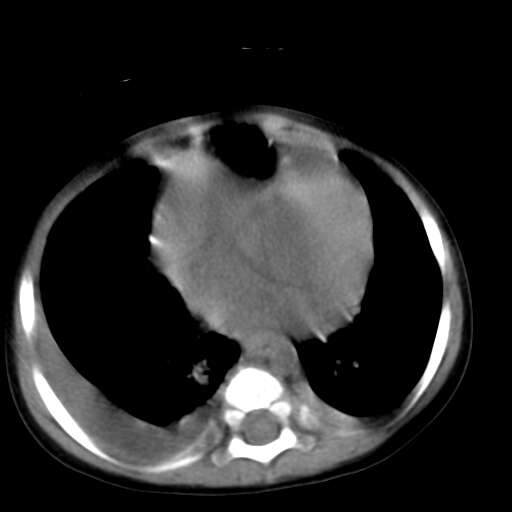

患儿1y,女,因支肺炎经dr检查发现前上纵膈占位而行ct检查,肿块与心血管脂肪间隙模糊消失,可见斑点状钙化,未见脂肪成分,双侧胸水,考虑侵袭性胸腺瘤

1、定位:前上纵隔,血管及头臂干前方,胸腺部位。

2、巨大实性肿块,其内见小片状低密度灶和少许点状钙化。

3、双侧胸腔积液,提示肿瘤恶性可能。

4、双肺下也背侧肺间质水肿改变。